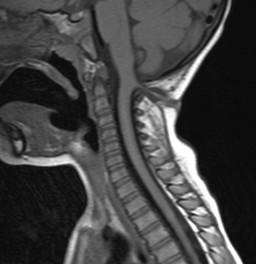

MMC CHIARI II

Tectal beaking, CC dysgenesis, hydrocephalus/colpocephaly, aqueductal stenosis, small posterior fossa with towering cerebellum, cerebellar tonsillar crowding and medullary kinking, syrinx

Fetal MR

Squared off frontal horns